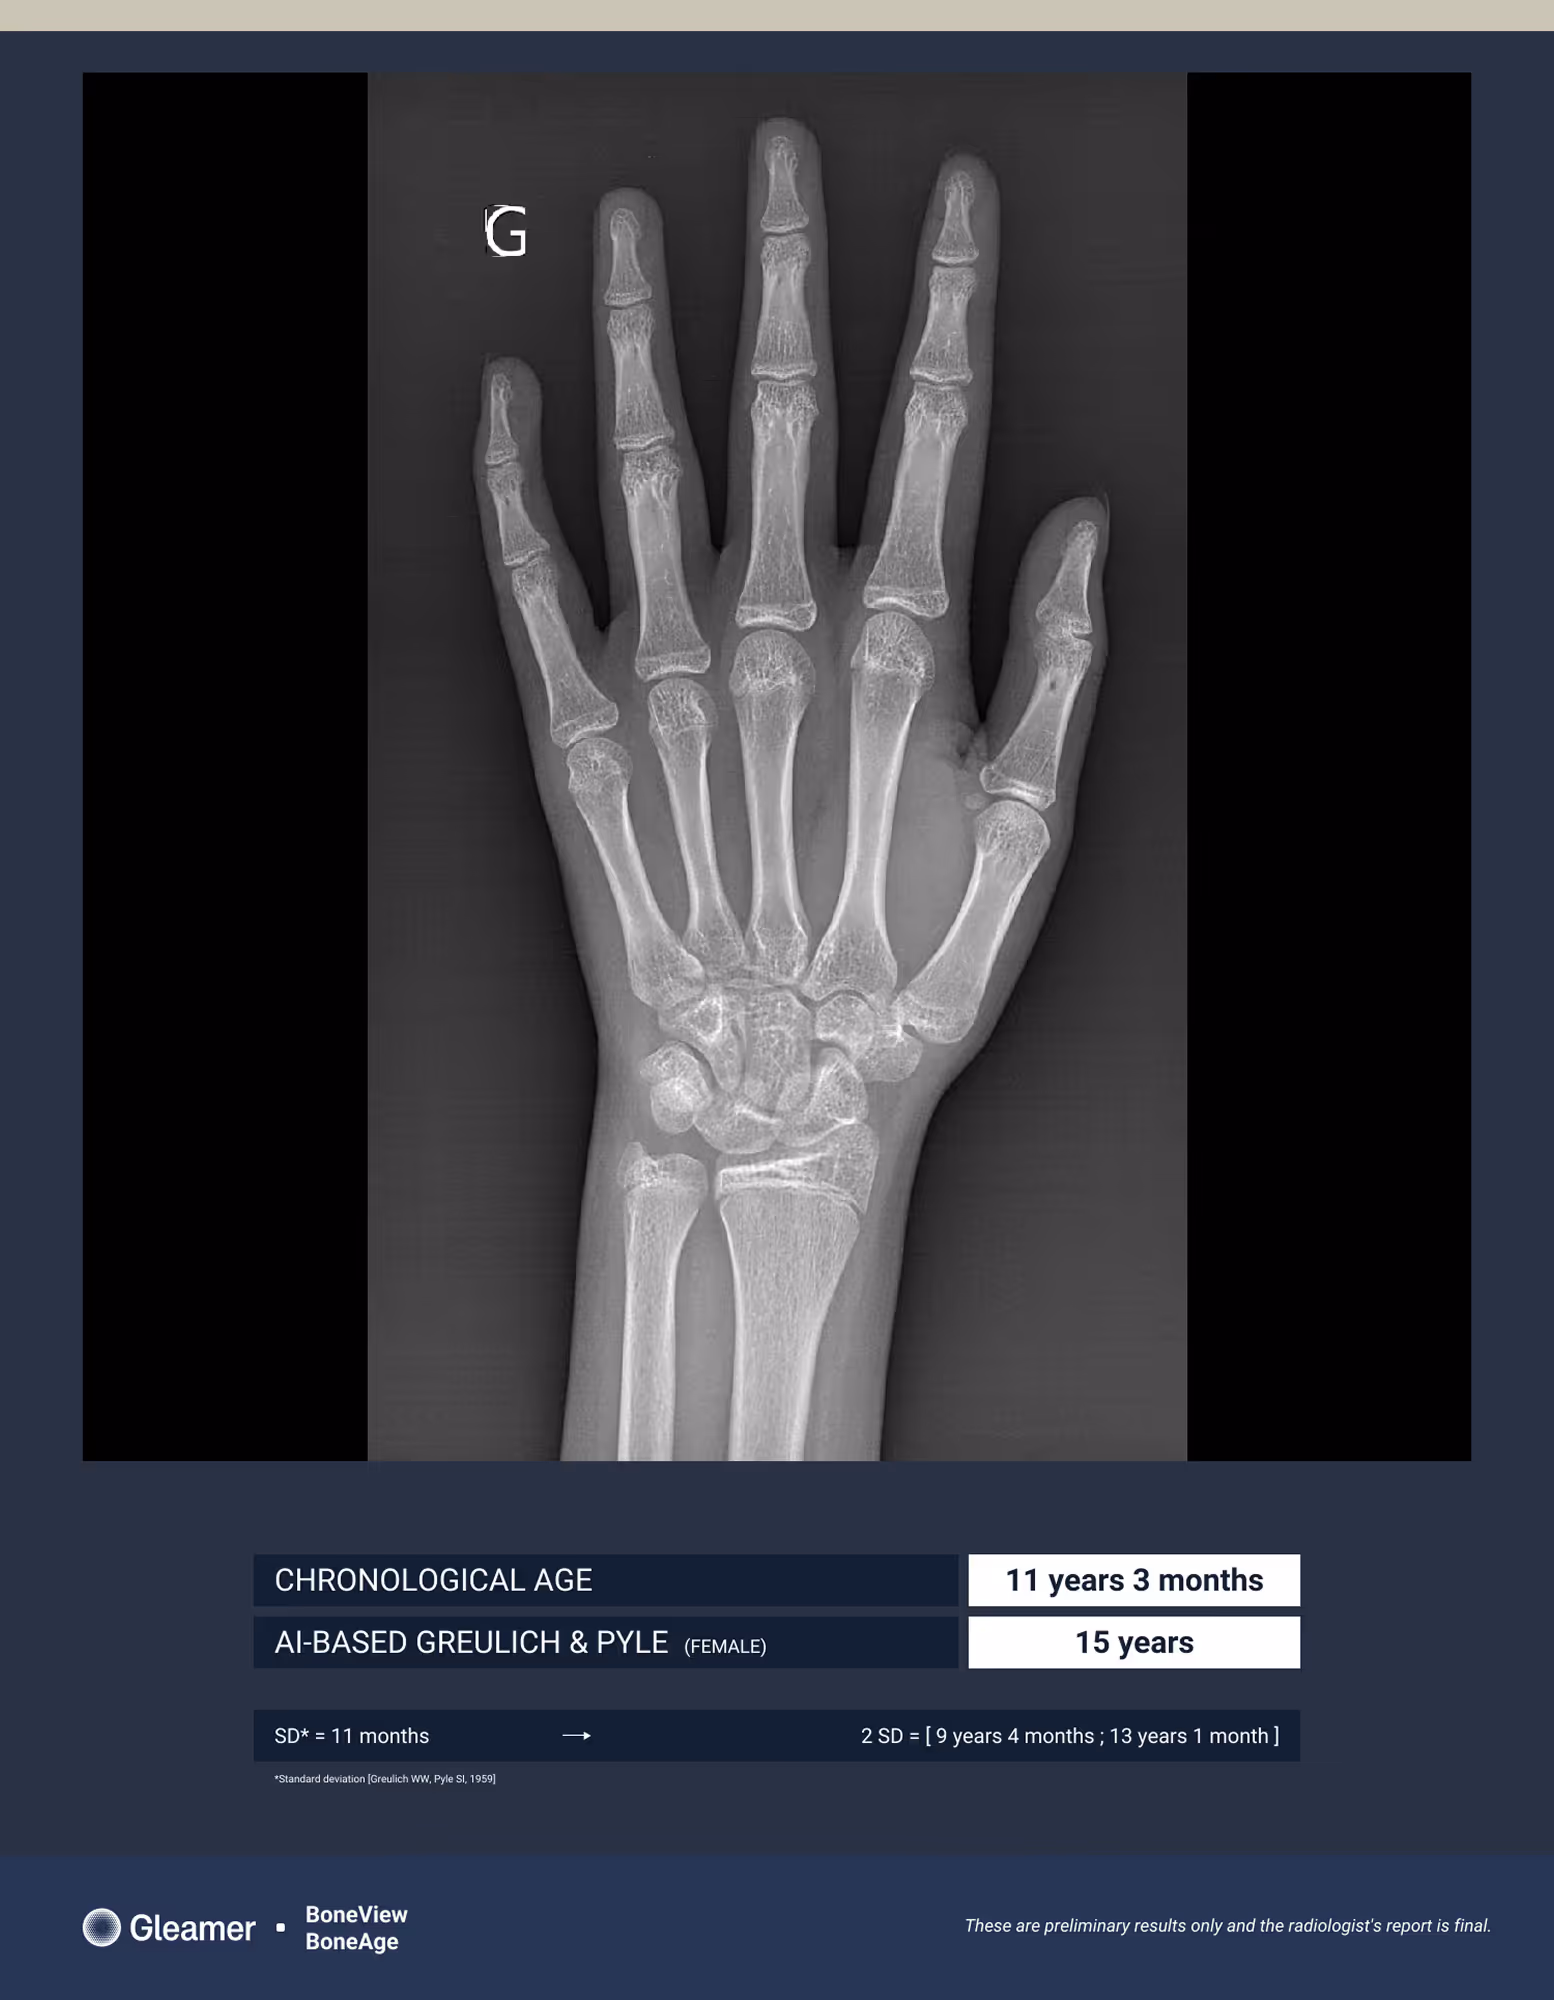

An 11-year-old girl presenting for bone age assessment due to signs of early puberty.

BoneAge analysis indicates an advanced bone age compared to the patient’s chronological age.

BoneAge automates bone age assessment using the Greulich & Pyle atlas method, the gold standard, helping radiologists detect an advanced or delayed age development, additionally saving valuable time while ensuring precision.

BoneAge is designed for frontal hand acquisition using the Greulich & Pyle method.